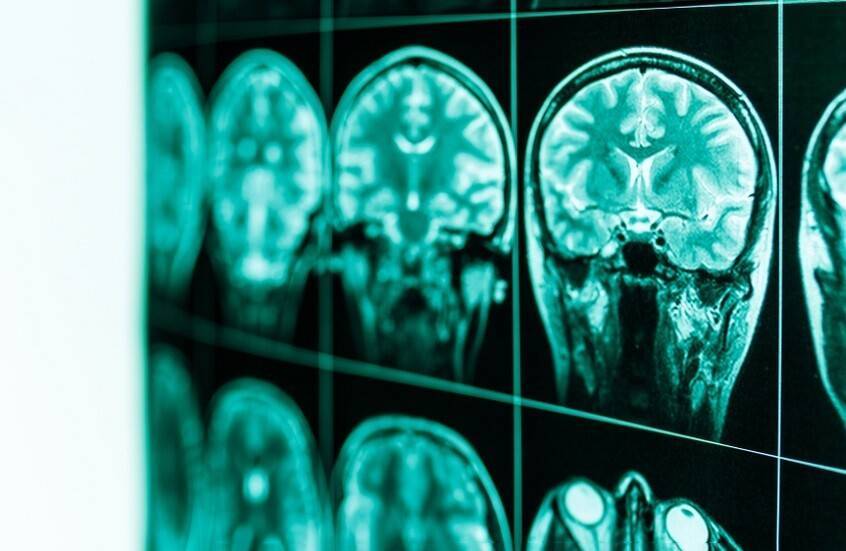

أظهرت الدراسة المنشورة في مجلة "ساينس أدفانسيز" كيف يدمر الكحول المناطق الرئيسية في الدماغ المسؤولة عن القدرات الإدراكية. وقد يفسر هذا الاكتشاف سبب صعوبة تعامل المدمنين على الكحول مع حالات الانتكاس.

واكتشف العلماء حدوث تغيرات كبيرة في أدمغة الفئران وتحديدا في منطقة تسمى "الجسم المخطط الظهري الإنسي" (dorsomedial striatum). وهذه المنطقة مسؤولة عن التخطيط والتفكير الاستراتيجي.